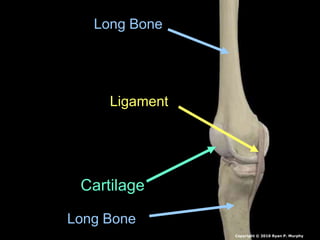

Long Bone

Cartilage

Ligament

Compact

Soft / Spongy

Yellow

Red

Blood